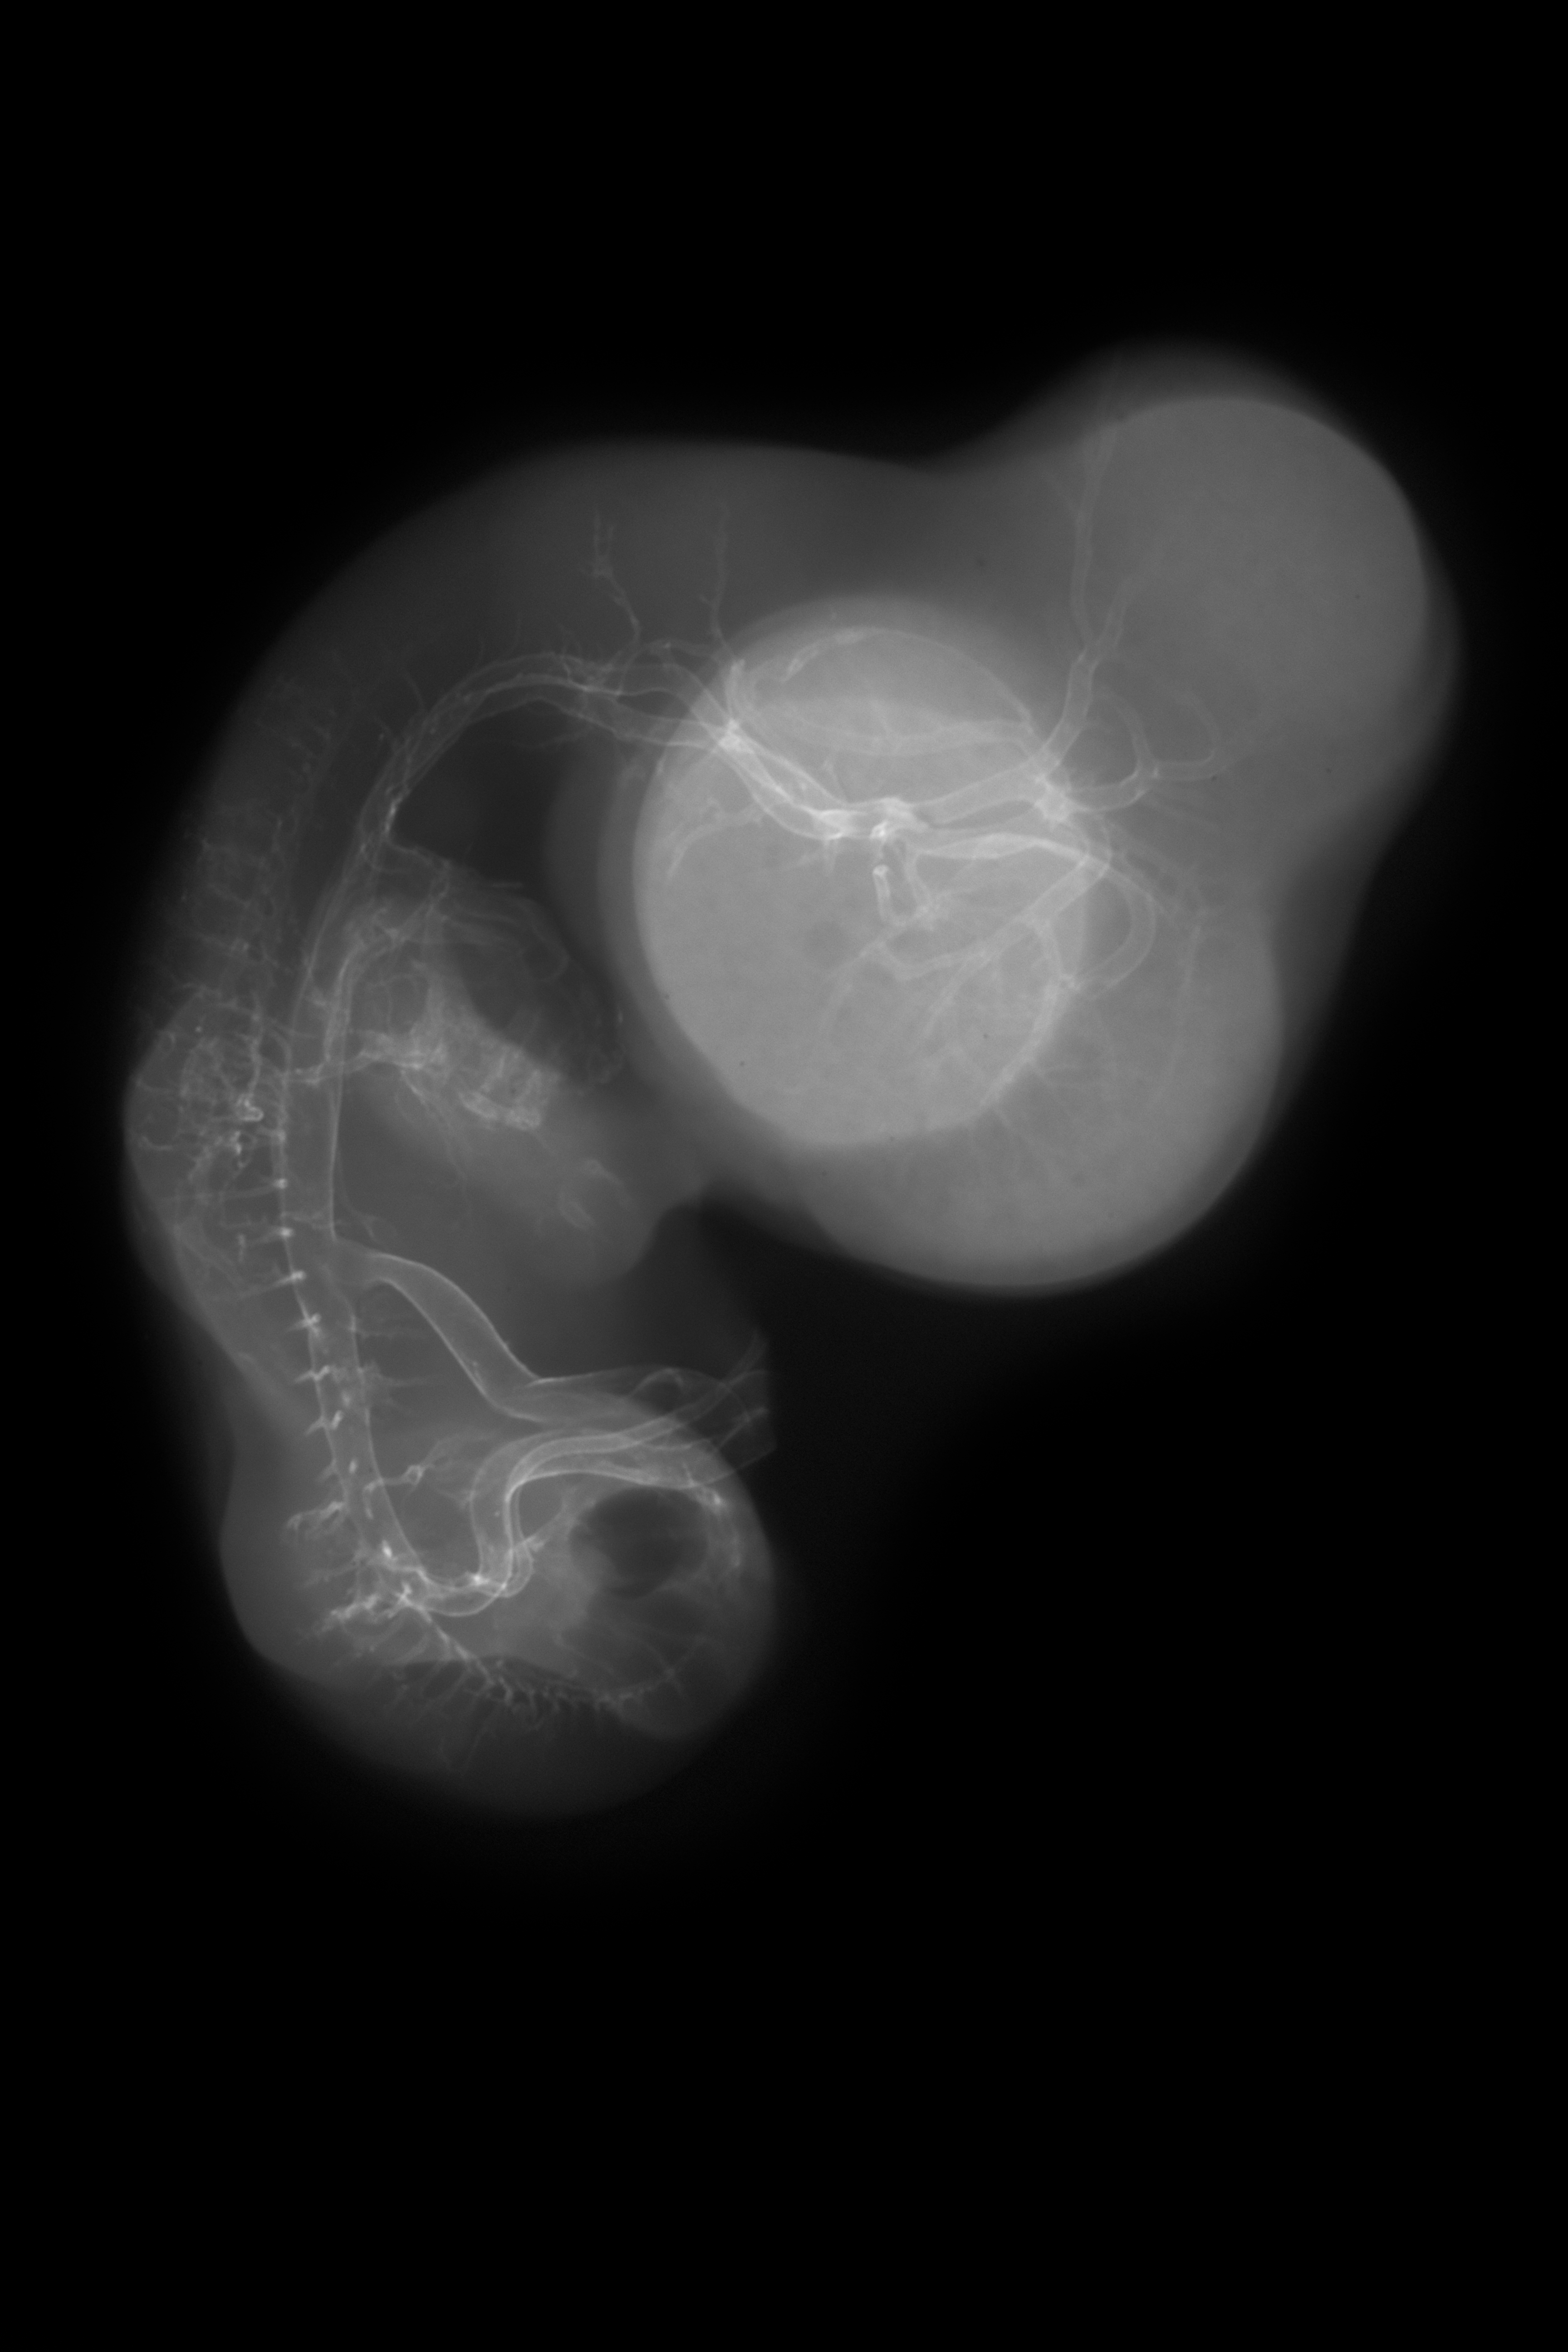

Chick Embryo Microangiography

Hamburger-Hamilton (HH) Stage 29 (approx. 6 - 6.5 days)

Stereo X-Ray Micrographs